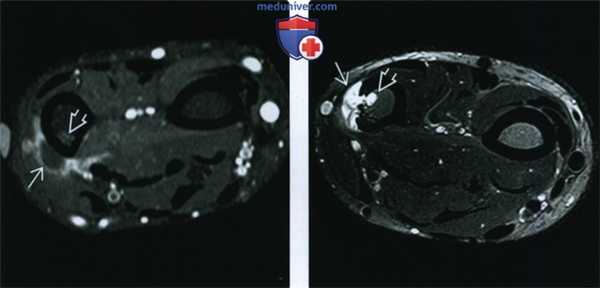

(Справа) Рентгенография в боковой проекции: типичный пример ОС проксимального отдела малоберцовой кости. Образование содержит остеоидный матрикс, характеризуется выраженной периостальной реакцией по типу «солнечной вспышки» и формированием матрикса в мягкотканном компоненте опухоли. Признаки поражения большеберцовой кости не визуализируются. (Слева) МРТ, аксиальная проекция, режим T1: ОС у этого же пациента изоинтенсивна по отношению к мышце, с низкоинтенсивными участками, соответствующими периостальной реакции по типу «солнечной вспышки».

(Справа) МРТ, аксиальная проекция, режим Т2 с подавлением сигнала от жира: более отчетливо визуализируется низкоинтенсивное костное образование в мягких тканях и периостальная реакция. Остальная часть ОС гиперинтенсивна по отношению к мышце. Визуализируются признаки отека, распространяющегося на многие сопряженные мышцы без явного патологического образования. Невозможно достоверно утверждать, что эти области свободны от опухоли. (Слева) МРТ, аксиальная проекция, режим Т1 с подавлением сигнала от жира, с контрастным усилением: интенсивное, неоднородное накопление контрастного вещества мягкотканным компонентом. Костный компонент опухоли сохраняет низкую интенсивность сигнала, поскольку представляет собой плотное костное образование. Тот факт, что мягкие ткани переднего отдела, гиперинтенсивные в режиме Т2 с подавлением сигнала от жира, здесь не накапливают контрастное вещество повышает вероятность отсутствия их опухолевого поражения.

(Справа) МРТ, аксиальная проекция, режим Т1, более проксимальный срез той же нижней конечности: визуализируются два критически важных признака: два патологических очага в большеберцовой кости. Сегментарные метастазы встречаются редко и могут появляться в основной кости или развиваться в области сустава.